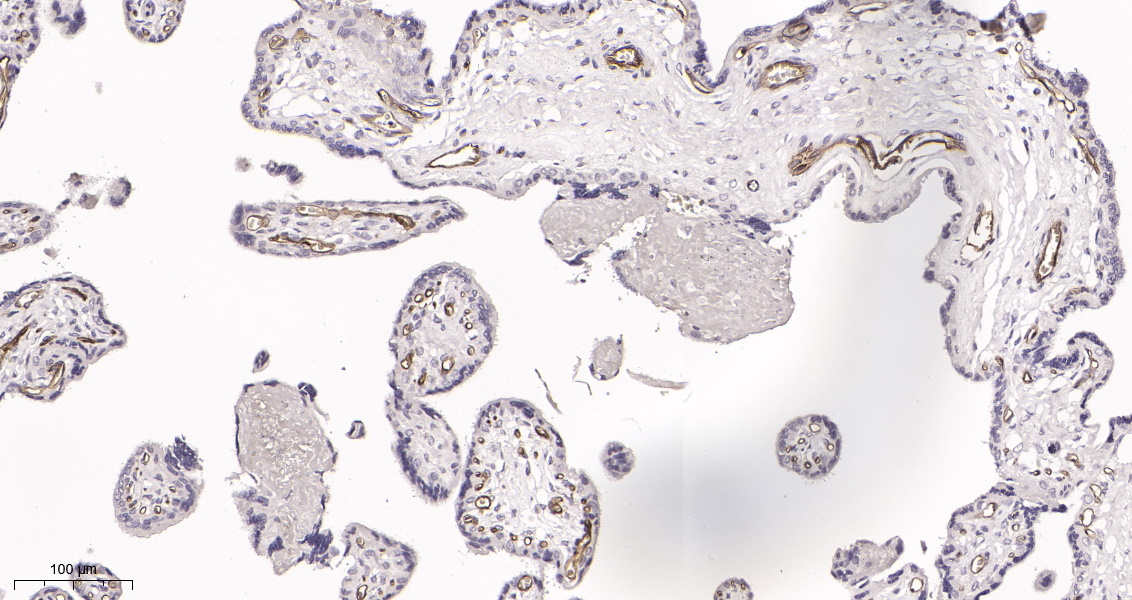

产品名称CD31 (19N16) Rabbit Monoclonal Antibody

推荐应用WB,IHC-P,IF-P,IF-F,IF-ICC,ELISA

稀释度IHC-P 1:200-1000, WB 1:1000-5000, IF-P/IF-F/IF-ICC 1:200-1000, ELISA 1:5000-20000

背景介绍The protein encoded by this gene is found on the surface of platelets, monocytes, neutrophils, and some types of T-cells, and makes up a large portion of endothelial cell intercellular junctions. The encoded protein is a member of the immunoglobulin superfamily and is likely involved in leukocyte migration, angiogenesis, and integrin activation. [provided by RefSeq, May 2010],

信号通路Cell adhesion molecules (CAMs);Leukocyte transendothelial migration.

功能function:This protein is a cell adhesion molecule expressed on platelets and at endothelial cell intercellular junctions.,online information:CD31 entry,online information:PECAM-1,online information:The Singapore human mutation and polymorphism database,PTM:Phosphorylated on Ser and Tyr residues after cellular activation.,similarity:Contains 6 Ig-like C2-type (immunoglobulin-like) domains.,tissue specificity:Long isoform predominates all tissues examined, isoform Delta12 was detected only in trachea and isoform Delta14-15 only in lung, isoform Delta14 was detected in all tissues examined with the strongest expression in heart.,